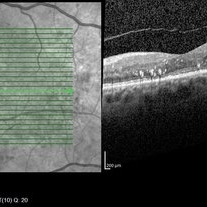

Diabetic Macular Edema Post One Intravitreal Anti-VEGF Dose

Decreased cystic changes and resolved subretinal fluid, lipid remains present.

Imaging device: Heidelberg Spectralis

Condition/keywords: anti-VEGF, diabetic macular edema